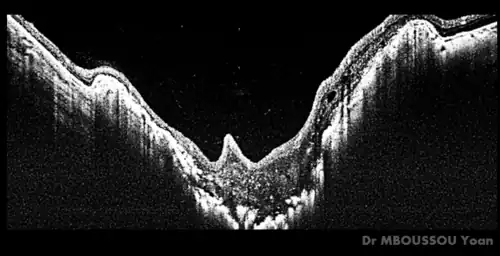

Morning glory syndrom met optische coherentietomografie (OCT)